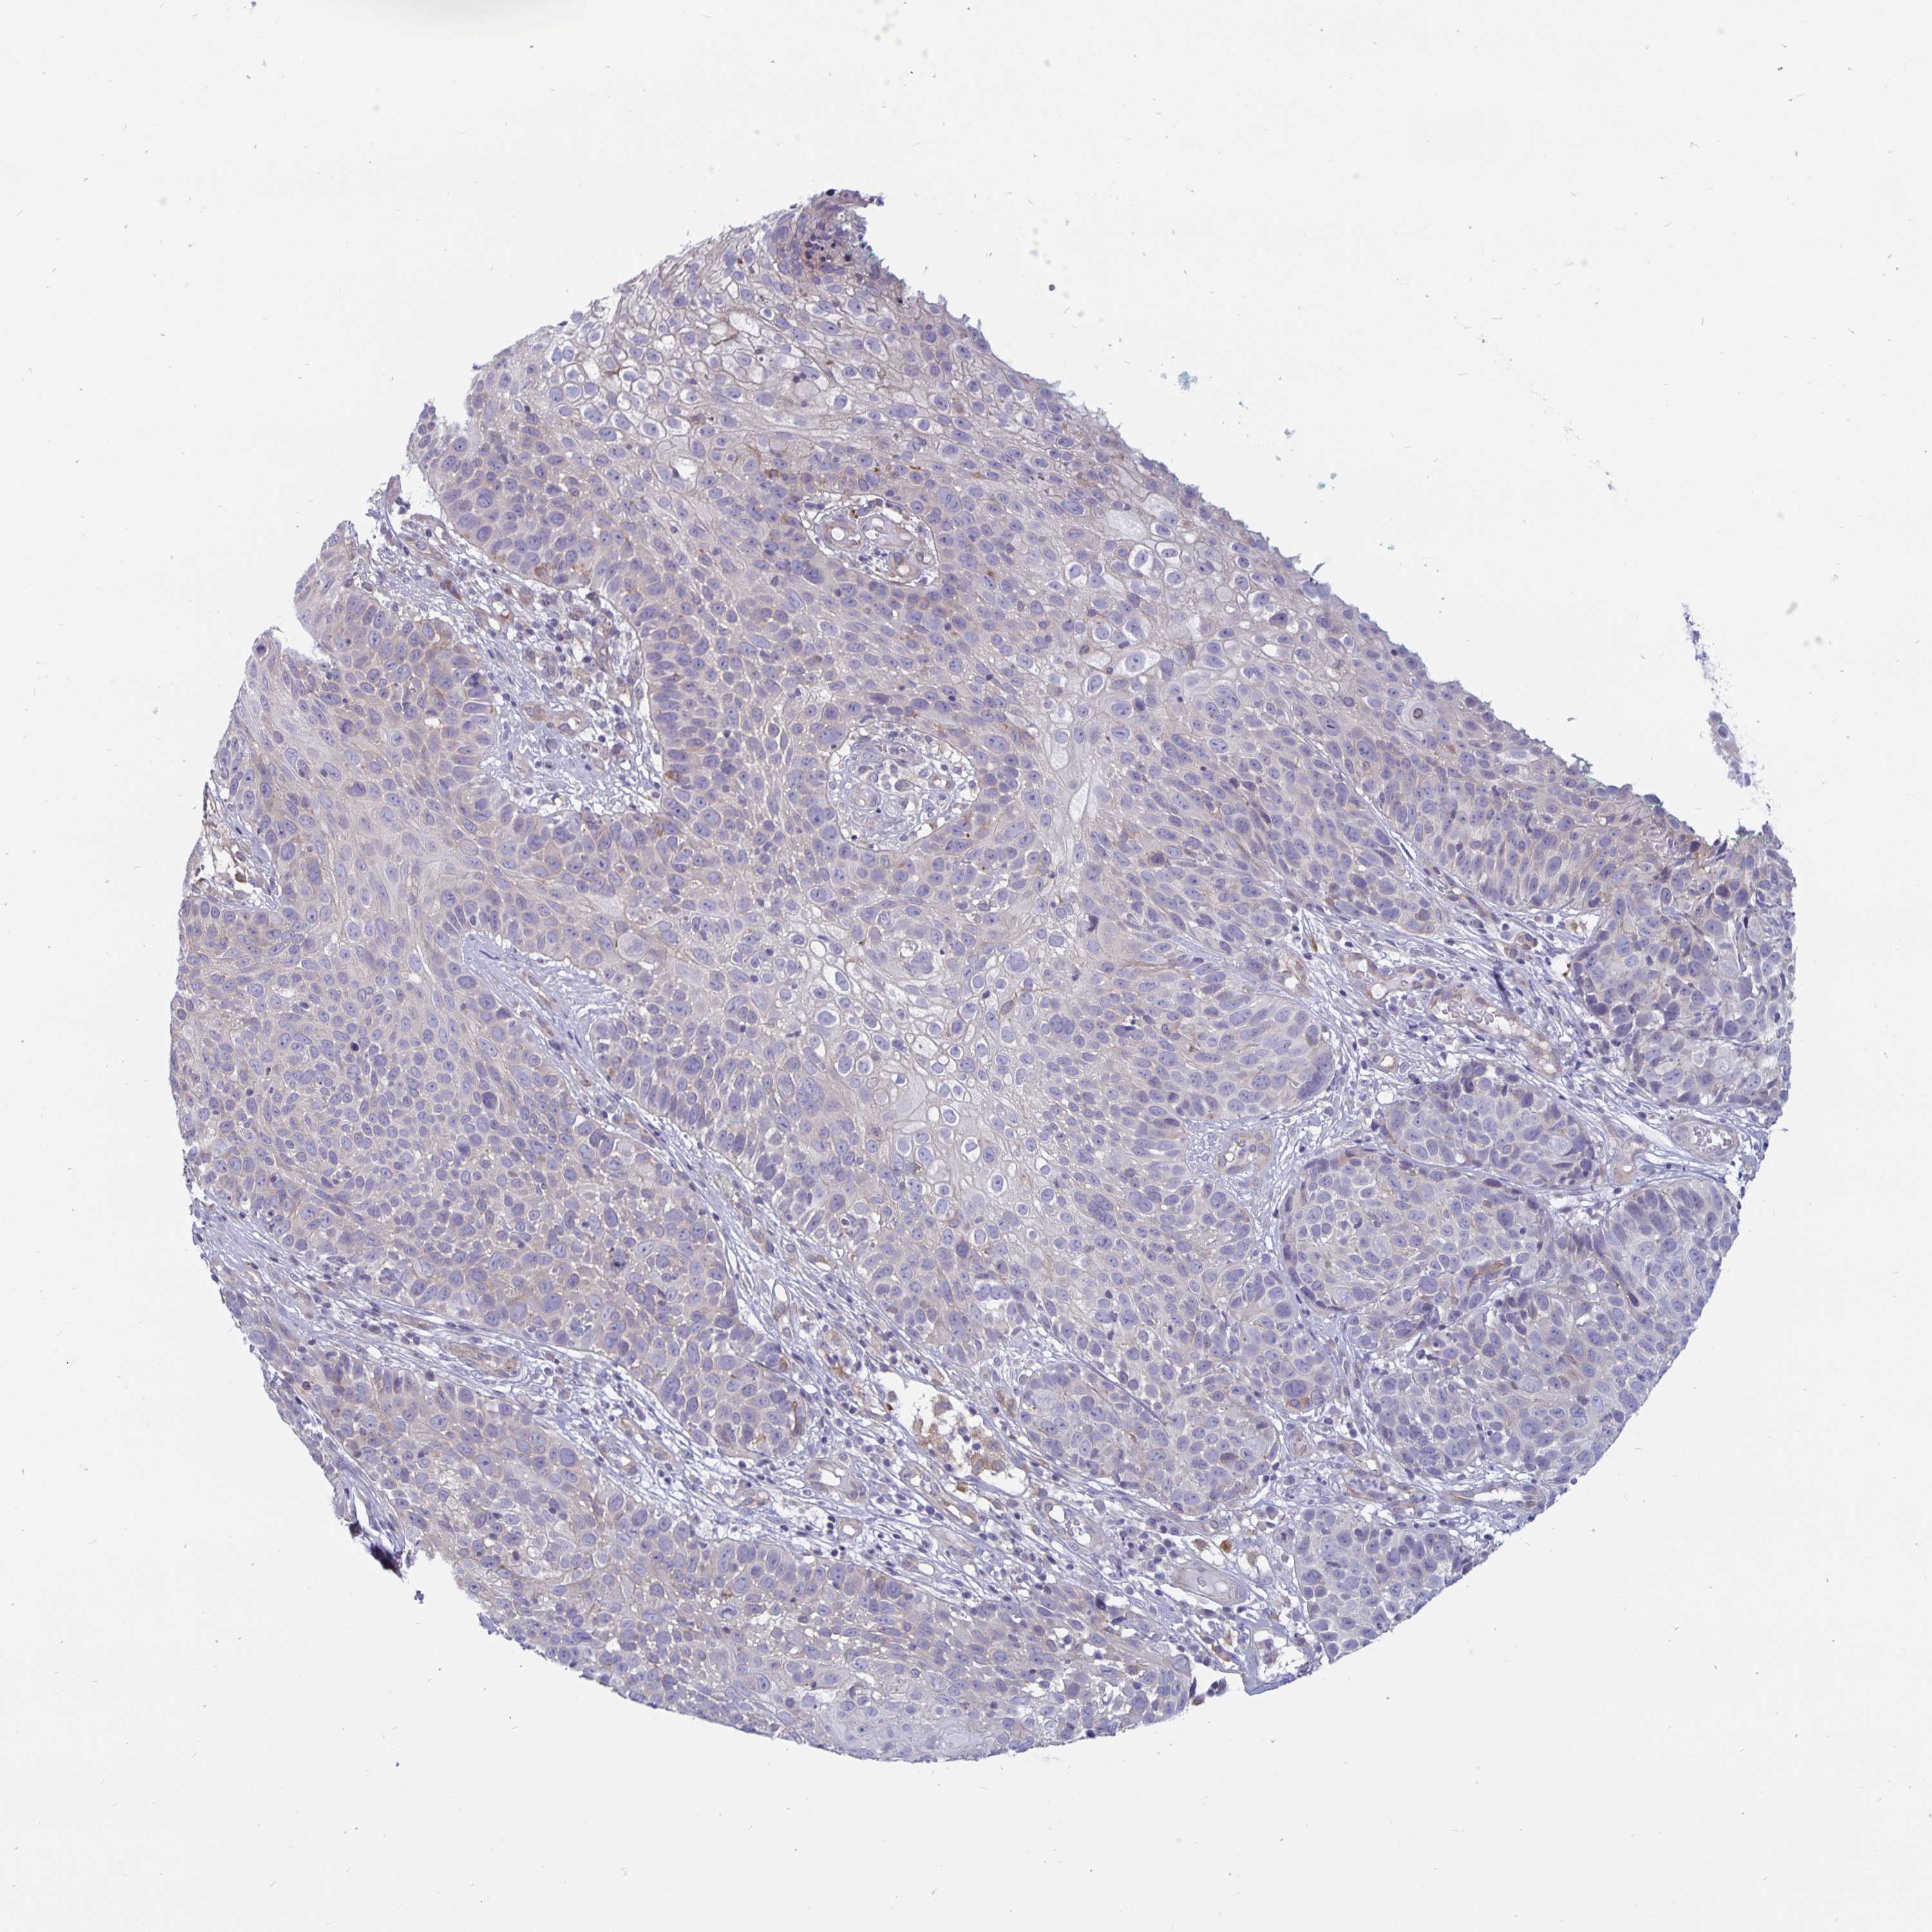

SKIN CANCER - Protein expressioni

A mouse-over function shows sample information and annotation data. Click on an image to view it in a full screen mode. Samples can be filtered based on level of antibody staining by selecting one or several of the following categories: high, medium, low and not detected. The assay and annotation is described here.

Antibody staining in the annotated cell types in the current human tissue is reported as not detected, low, medium, or high, based on conventional immunohistochemistry profiling in selected tissues. This score is based on the combination of the staining intensity and fraction of stained cells.

Each image is clickable and will lead to virtual microscopy that enables deeper exploration of all samples and also displays staining intensity scores, fraction scores and subcellular localization as well as patient and tissue information for each sample.

Antibody HPA043907

Staining

High

Medium

Low

Not detected

Basal cell carcinoma

Squamous cell carcinoma, NOS